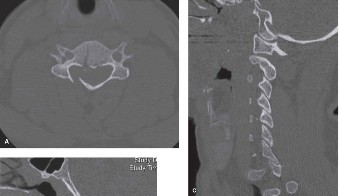

of injury was a fall down the stairs associated with loss of consciousness. Assuming that the patient has a cervical spine injury, there is 10% to 15% chance that he has a noncontiguous concomitant fracture elsewhere in the spine. Thus, obtaining imaging of only the cervical spine would not be prudent. Multidetector CT scans have largely become the initial imaging modality in most trauma centers. A head-to-toe scan can be acquired in a short period of time and can be used to evaluate the cervical, thoracic, and lumbar spine as a screening tool. A CT scan of the cervical spine would be inadequate as one can miss concomitant injuries. An MRI might be useful in the setting of a neurological injury, but it would not be the initial imaging test. Furthermore, an MRI of other regions of the spine would not be indicated unless an injury was detected on CT. Flexion–extension views are generally not advisable due to their lack of sensitivity in the acute setting. The cervicothoracic junction is also quite difficult to visualize in the flexion–extension views. CT scan images of his cervical spine are shown inFigures 1–29 to 1–31. The next step in management should be: 1. High-dose methylprednisolone

Figure 1–29

Figure 1–30

Figure 1–31

Discussion

The correct answer is (C). The patient has a unilateral right C7 facet dislocation with a small associated fracture. The use of high-dose methylprednisolone for acute spinal cord injury, while frequently discussed, remains controversial with limitations in the evidence supporting its use. At most, it is a treatment option in the setting of a spinal cord injury. That being said, the above patient’s examination reveals a C7 root injury, not a spinal cord injury. A reduction of the dislocation would be a reasonable next step in this patient as he is awake, alert, and able to cooperate with an examination. An awake closed reduction has been demonstrated to be both safe and effective in treating cervical dislocations. While a successful closed reduction would not obviate the need for surgical stabilization, it can provide expeditious neurological decompression (via realignment) and enable surgery to be performed in a less urgent manner on a reduced spine. One reported risk of closed reduction is the risk of disc herniation and subsequent neurological deterioration. This has led some surgeons to obtain a prereduction MRI to determine if a disc herniation is present with the dislocation. For some, the presence of a disc herniation prompts an anterior discectomy prior to reduction. However, an upright MRI would not be advisable. The patient may eventually undergo surgical stabilization but not until the spine is reduced. Stabilization in a nonreduced position